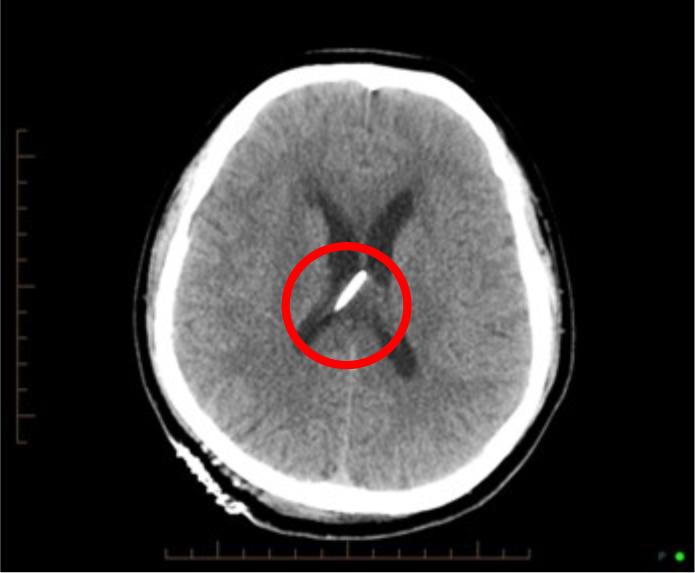

Pictured above is a scan of the patient’s brain. The white area circled in red shows the placement of the shunt following the first surgery.